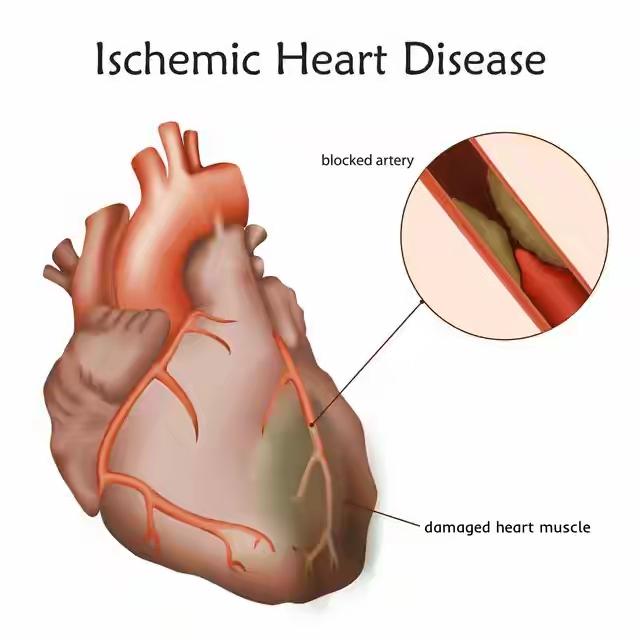

38岁爸爸打10分钟羽毛 球突然心梗!同一天另一位爬山后被送医,医生严肃提醒:运动可当不了万能通行证,这些细节可能致命! 那天急诊室里,一下子就送来了两位38岁的爸爸。其中一位是陪着孩子打了大概10分钟羽毛球,正玩得热闹时,突然捂着胸口疼得直不起腰,直接倒在了地上。明明一年前就查出冠脉有60%的狭窄,却一直没好好治疗,总想着靠运动能把血管养回来。另一位则是周末带孩子去爬山,爬完山后胸口像压了块大石头似的疼,被家人紧急送到医院,一检查才发现,他的血糖和血脂早就高得离谱。 医生看着这两个病例,总结出三个最容易要命的“导火索”:第一,突然做太剧烈的运动,血管里的斑块可能会被“冲”破;第二,本身血管就有狭窄,运动时心脏要跳得更快,供血跟不上就会出问题;第三,天冷的时候,血管一收缩,也容易引发危险。更让人担心的是,很多人平时就踩了这些“坑”——熬了大夜还硬要去运动,感冒还没好利索就急着动,或者好几天不运动,周末突然猛练一场。 记住四个“保命”的字:循序渐进!运动的时候,要是还能完整说一句话,那强度就算安全的。要是感觉胸口闷得慌,或者左边肩膀也跟着疼,赶紧停下来别动。这两位爸爸拿自己的命换来的教训:孩子要的是一个能健健康康陪他长大的爸爸,而不是朋友圈里晒运动打卡的“达人”。 快转发给那个总说“我身体好着呢,没事”的朋友!你身边有没有那种总爱说“我能行,运动就没事”的“运动狂人”?他们的故事说不定就能让更多人明白这个道理——健康活着,比什么都重要啊!